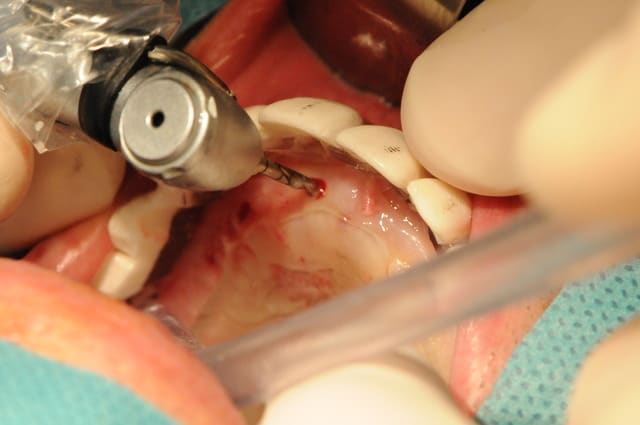

C'est une question que je me pose, car je viens de faire un cas comme ça mercredi matin.

Au départ j'avais plutôt prévu de faire un lambeau d'accès comme d'habitude avec sutures et tout et tout...

Étant donné que j'avais une autoroute en matière de crête osseuse, je me suis dis " et puis zut, restons dans le couloir prothétique et plantons en aveugle".

Une bonne connaissance du scan était nécessaire, et des petits contrôles radios pendant la pose bien évidemment pour connaître la longueur de perçage et savoir quand mon implant allait être juxta-crestal.

- J'ai trouvé ça super de ne pas avoir à faire de sutures

- l'un des implants est volontairement incliné car il vient longer le plancher sinusien. Je n'avais pas envie de faire de Summers et le patient ne voulait pas de soulevé de sinus.

Est ce que les cellules gingivales vont réduire mes chances d'ostéointégration ?

Je ne pense pas qu'on puisse le faire chez tous le monde, mais là, j'avais de la crête, de la gencive attachée et de l'os à profusion...